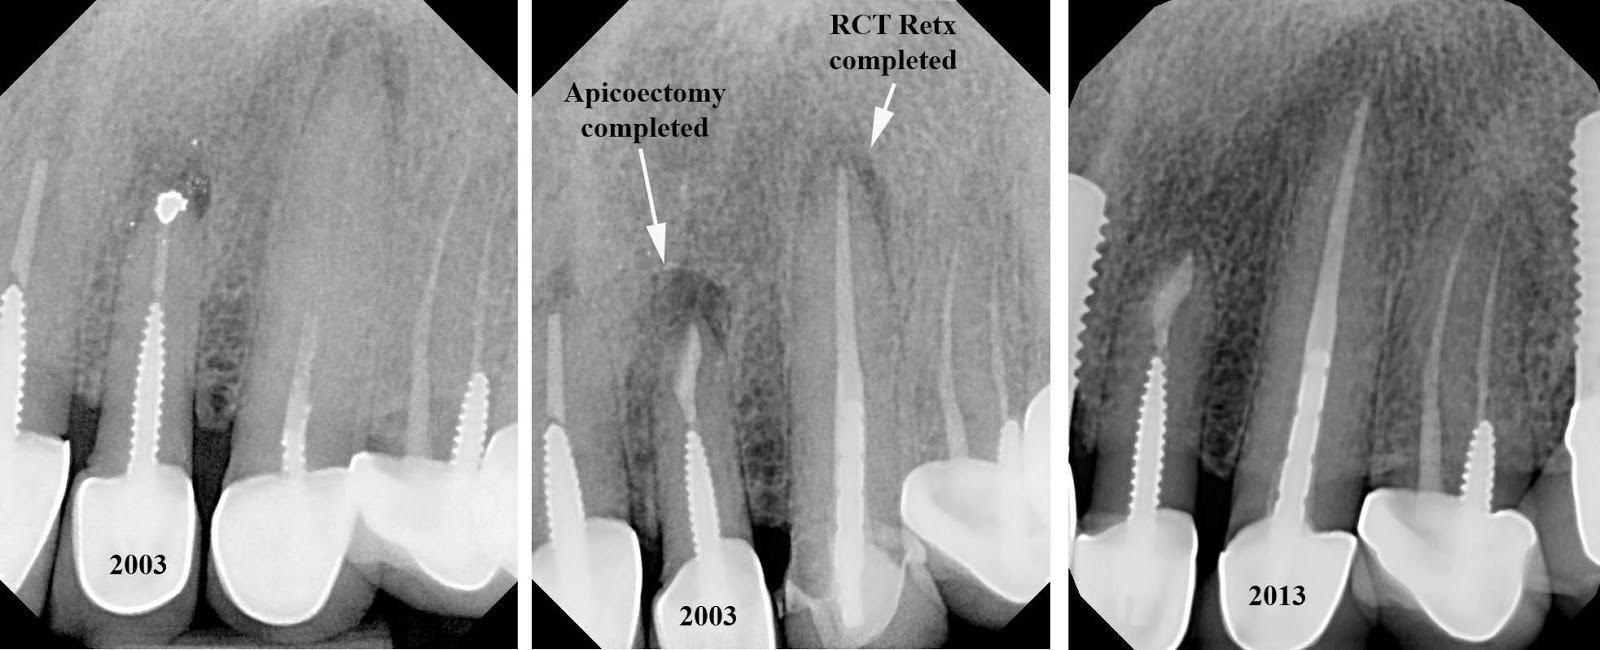

From www.theendoblog.com

The Endo Blog 10 Yr Success of Apicoectomy & RCT Retreatment Rct Retreatment Steps Nonsurgical retreatment procedures confirm mechanical failures, previously missed canals or radicular subcrestal fractures. Root canal treatment is carried out by your dentist over 2 or more appointments. When a root canal fails, endodontic retreatment is a dental procedure that redos the root canal to. Importantly, disassembly and corrective procedures allow Retreatment is usually more complicated than initial root canal treatment. Rct Retreatment Steps.